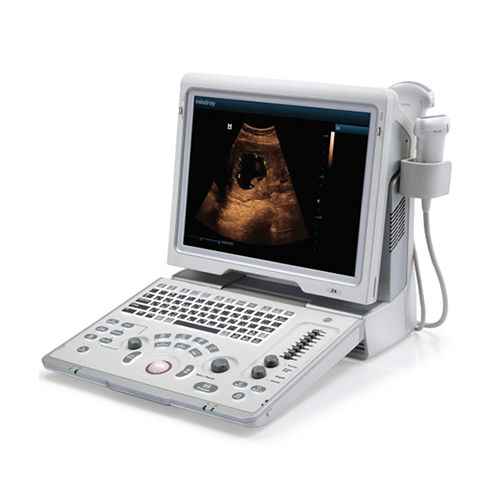

Description

GE Vivid 7 Imaging Modes

GE Vivid 7 Features: